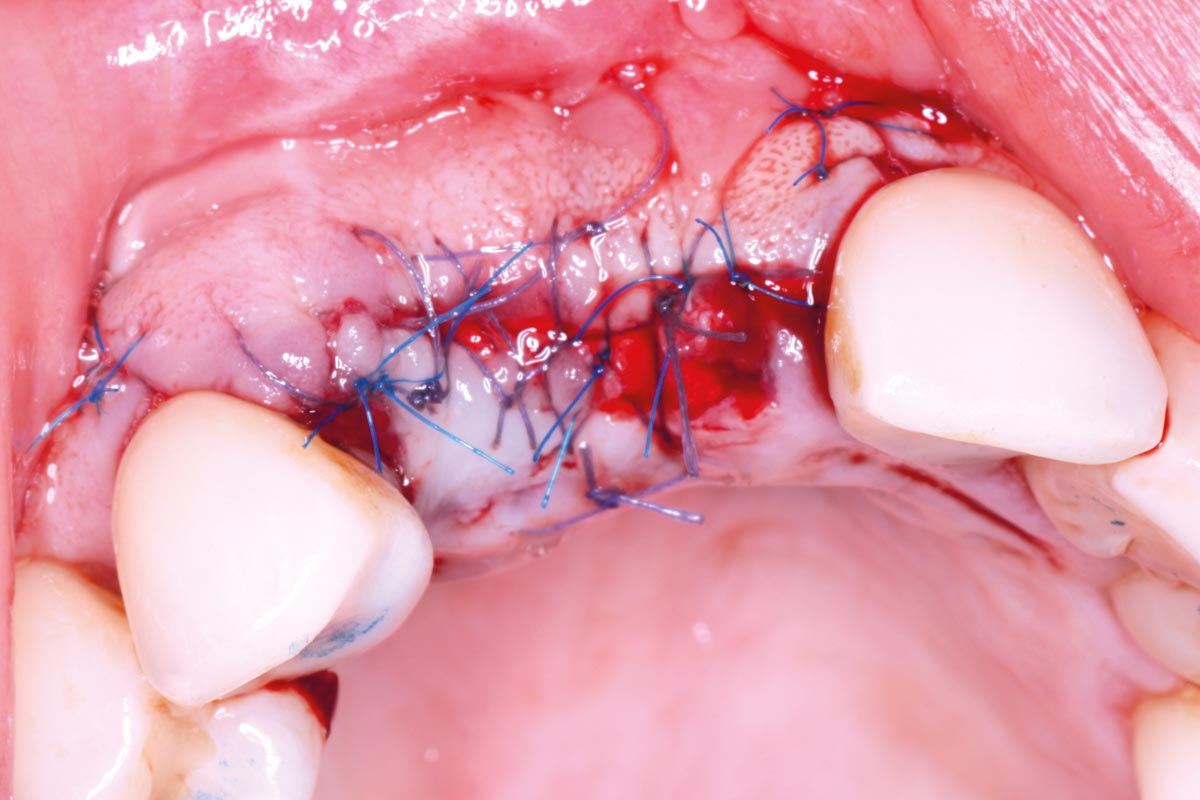

06/10 - Jason® membrane was stabilized with two interrupted sutures on the palatal aspect, and with two pins in the buccal aspect of the defectMaxillary bone reconstruction in the anterior area with cerabone® and Jason® membrane - Dr. P.-Y. Gegout & Prof. O. Huck

07/10 - Interrupted sutures with 5-0 resorbable sutures on the crest and 6-0 non-resorbable sutures for the releasing incisionsMaxillary bone reconstruction in the anterior area with cerabone® and Jason® membrane - Dr. P.-Y. Gegout & Prof. O. Huck